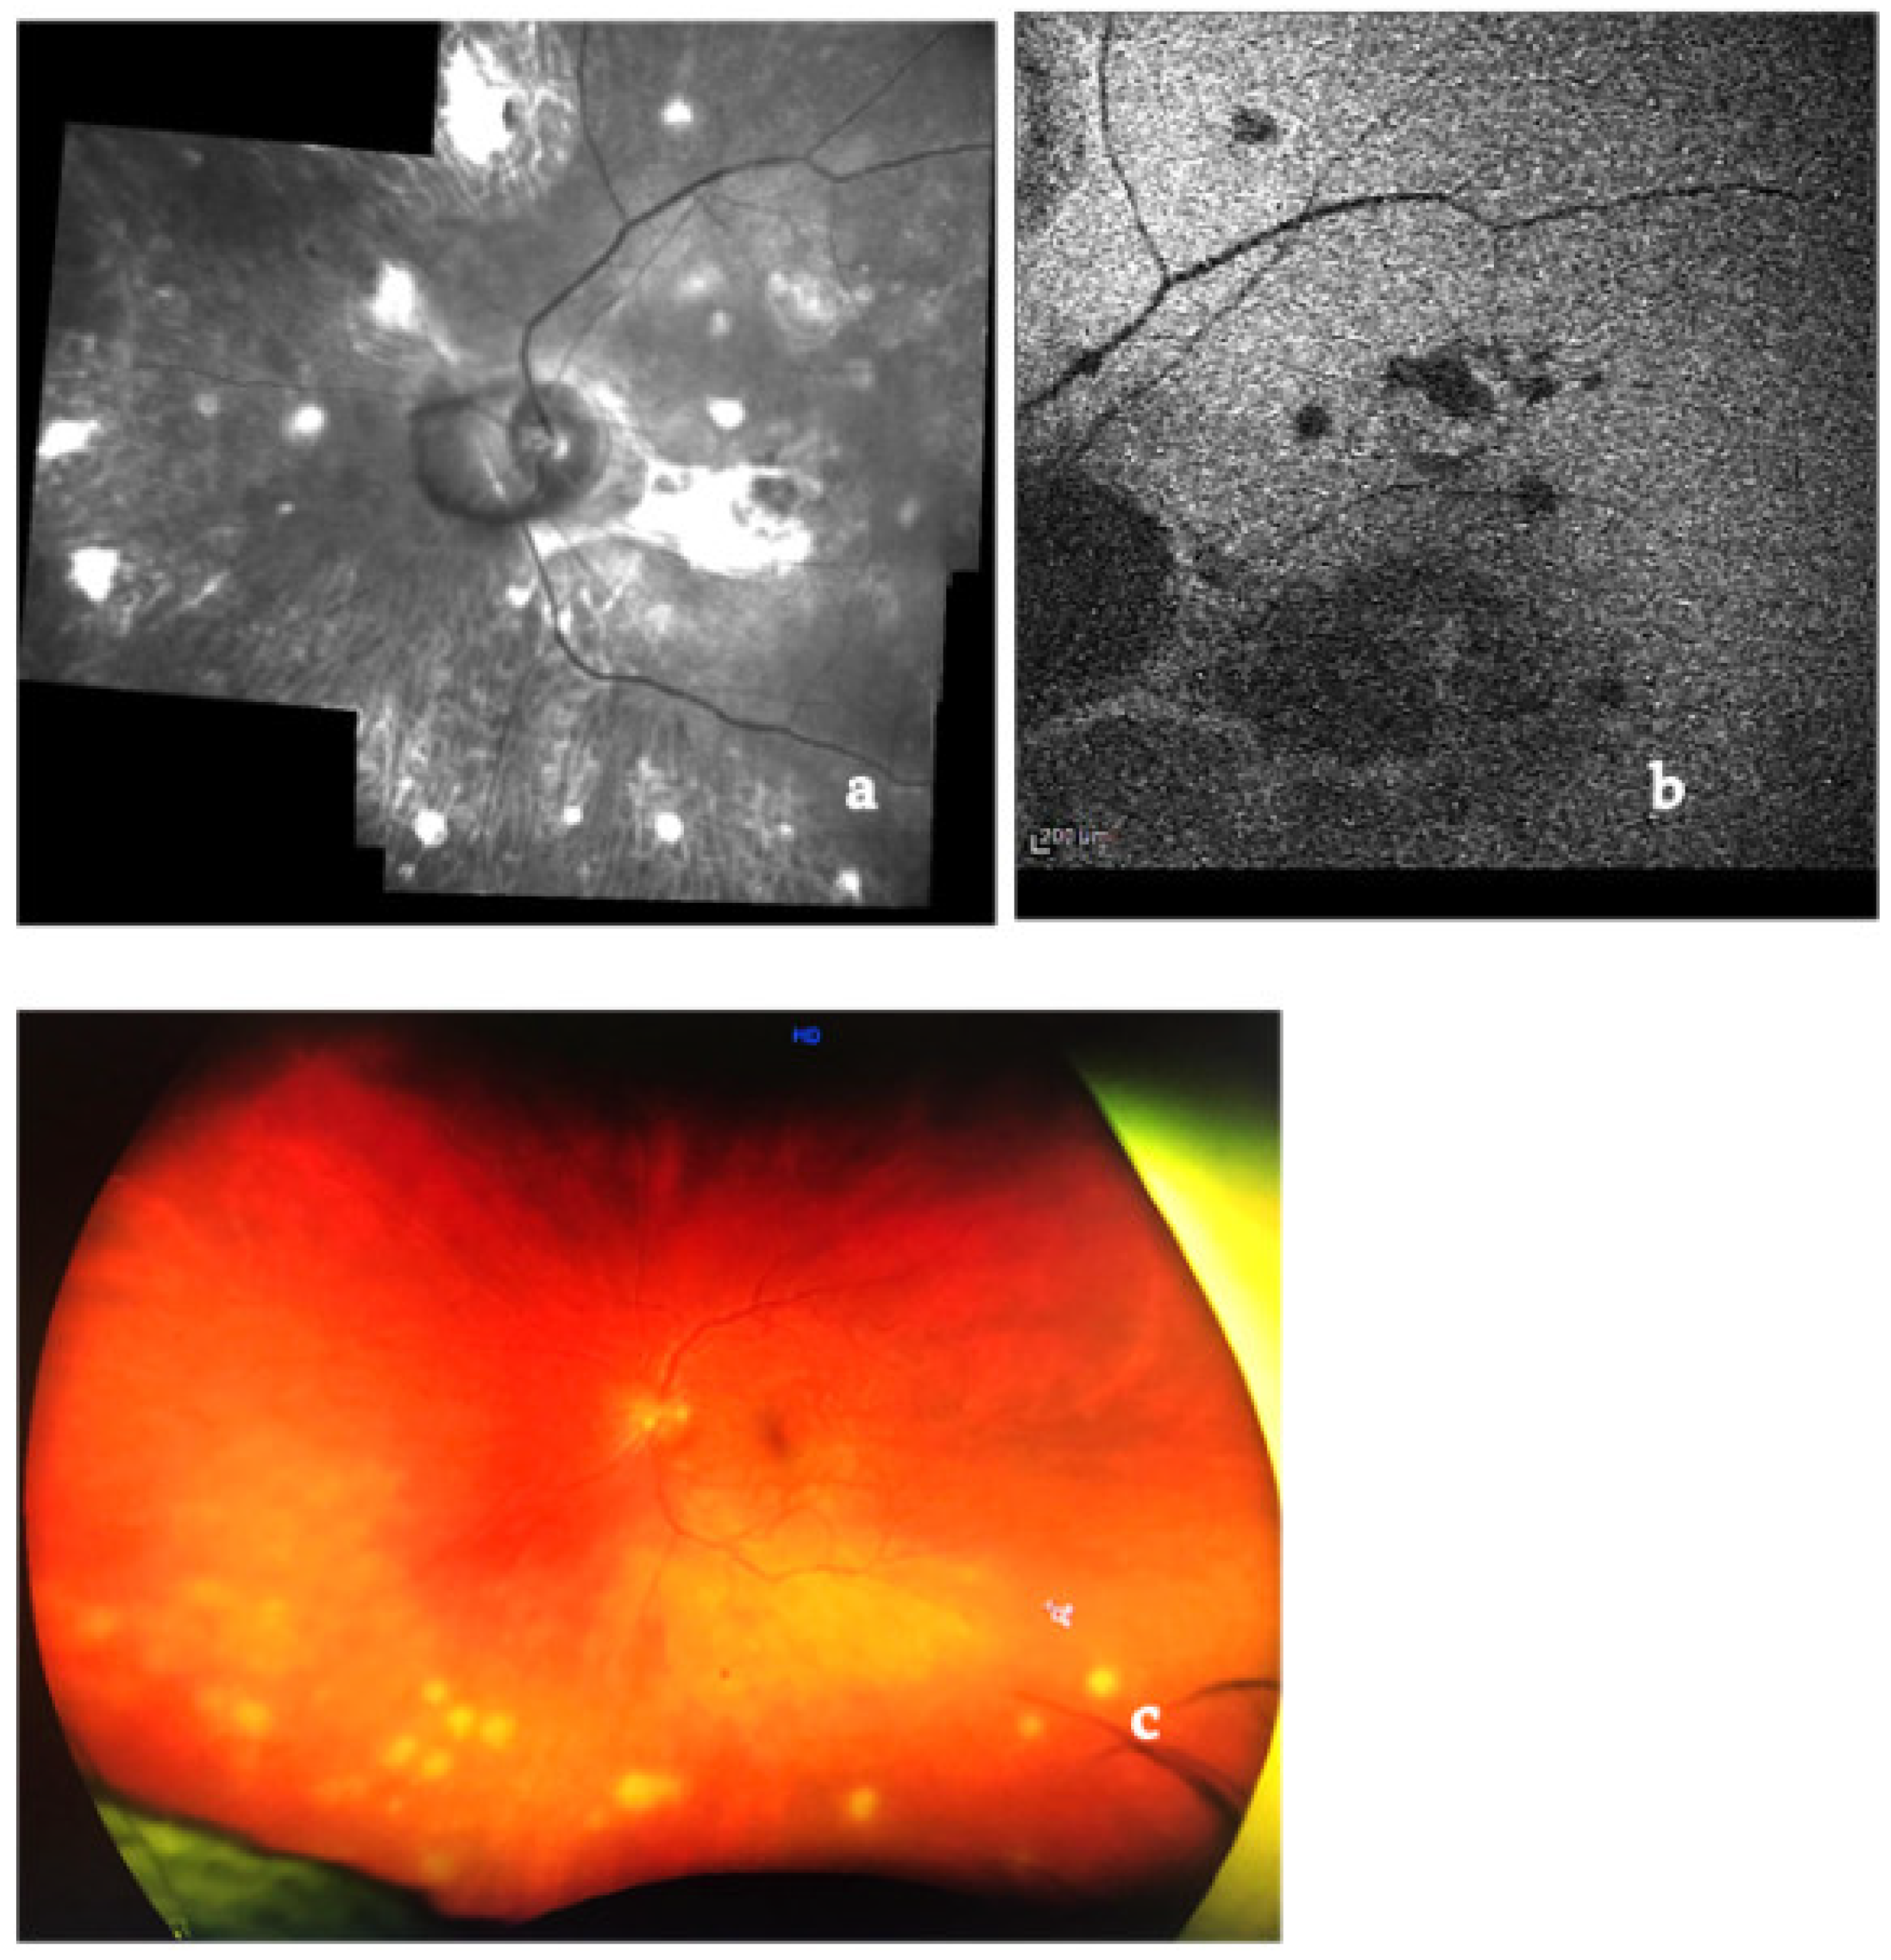

- Mahendradas, P.; Maruyama, K.; Mizuuchi, K.; Kawali, A.; Kitaichi, N. Multimodal Imaging in Ocular Sarcoidosis. Ocul. Immunol. Inflamm. 2020, 28, 1205–1211. [Google Scholar] [CrossRef]

- El Ameen, A.; Herbort, C.P., Jr. Comparison of Retinal and Choroidal Involvement in Sarcoidosis-related Chorioretinitis Using Fluorescein and Indocyanine Green Angiography. J. Ophthalmic Vis. Res. 2018, 13, 426–432. [Google Scholar] [CrossRef] [PubMed]

- Modi, Y.S.; Epstein, A.; Bhaleeya, S.; Harbour, J.W.; Albini, T. Multimodal imaging of sarcoid choroidal granulomas. J. Ophthalmic Inflamm. Infect. 2013, 3, 58. [Google Scholar] [CrossRef]

- Leder, H.A.; Campbell, J.P.; Sepah, Y.J.; Gan, T.; Dunn, J.P.; Hatef, E.; Cho, B.; Ibrahim, M.; Bittencourt, M.; Channa, R.; et al. Ultra-wide-field retinal imaging in the management of non-infectious retinal vasculitis. J. Ophthalmic Inflamm. Infect. 2013, 3, 30. [Google Scholar] [CrossRef]

- Campbell, J.P.; Leder, H.A.; Sepah, Y.J.; Channa, R.; Do, D.V.; Nguyen, Q.D. Wide-field retinal imaging in the management of noninfectious posterior uveitis. Am. J. Ophthalmol. 2012, 154, 908–911. [Google Scholar] [CrossRef]